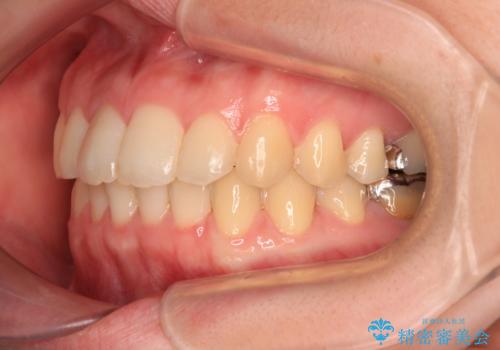

デコボコ歯列をきれいに インビザラインによる矯正治療

- 上下歯列全体のデコボコを気にして来院された患者様です。

主に下顎歯列全体の後方移動とIPR(歯と歯の間を削る)によってデコボコが解消するように設計し、インビザラインにより治療を行うこととしました。

1年半程度で終了するのではないかと予想しましたが、途中1年以上の来院がなく、トータルで3年の時間がかかってしまいました。

前歯のデコボコはより改善することが望ましい状態でしたが、患者様の希望により終了することとなりました。